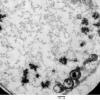

4 AXONAL DEGENERATION

3 Electron Microscopy